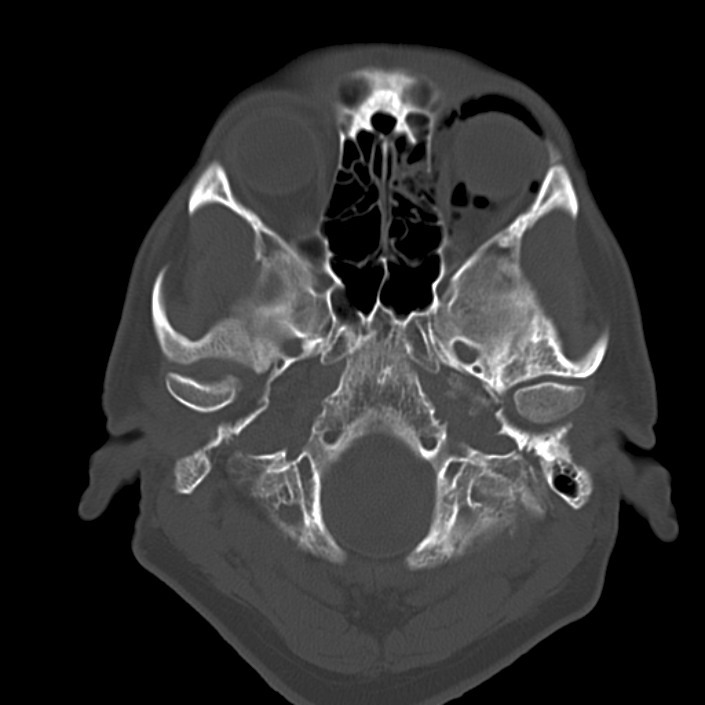

| current | 15:17, July 9, 2024 | 705 × 705 (128 KB) | Mohammad.Pakravan (talk | contribs) | CT scan showing the black eyebrow sign in the left orbit. Image courtesy of Radiopedia. Bickle I, Black eyebrow sign - orbital blow-out fracture. Case study, Radiopaedia.org (Accessed on 04 Jul 2024) https://doi.org/10.53347/rID-22525 |